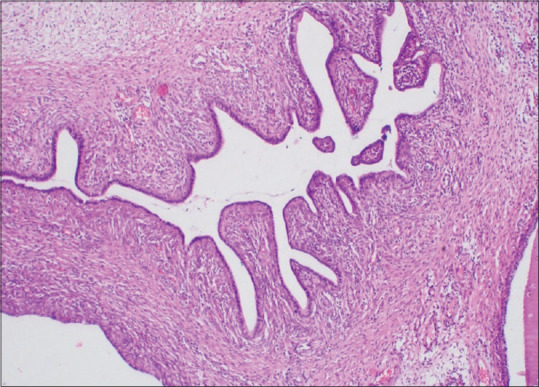

宫颈腺纤维瘤是一种极为罕见的良性苗勒氏混合性肿瘤,包括良性上皮组织和间质组织。世卫组织2020年对女性生殖道的分类甚至没有将腺纤维瘤作为一个单独的实体。一位50多岁的绝经后女性表现为每个阴道出血。检查发现多发性宫颈息肉。宫颈息肉的组织病理学提示宫颈腺纤维瘤,由于没有有丝分裂图形和细胞异型性。有时甚至分化良好的腺肉瘤也可能被误诊为腺纤维瘤。免疫组织化学标记有助于区分腺肉瘤和腺纤维瘤。没有典型的临床或影像学特征强烈提示诊断。虽然腺纤维瘤是一种良性肿瘤;然而,它仍被发现侵袭子宫肌层和盆腔静脉,复发和转移。对所有宫颈肿瘤进行详细的组织病理学检查是至关重要的,不仅可以排除恶性病变,而且可以排除腺纤维瘤,无论临床症状如何。

Adenofibroma of the cervix is an extremely rare benign Mullerian mixed tumor, which contains both benign epithelial and mesenchymal tissue. The WHO 2020 classification of the female genital tract does not even include adenofibroma as a separate entity. A postmenopausal lady in her mid-50s presented with bleeding per vagina. On examination, there were multiple cervical polyps. Histopathology of cervical polyps suggested adenofibroma of the cervix due to the absence of mitotic figures and cellular atypia. Sometimes even well-differentiated adenosarcomas can be misdiagnosed as adenofibroma. Immunohistochemistry markers help in differentiating adenosarcoma from adenofibroma. There are no typical clinical or imaging characteristics that strongly suggest the diagnosis. Although adenofibroma is a benign tumor; still it has been found to invade the myometrium and pelvic veins, relapse, and metastasize. It is crucial to perform a detailed histopathological examination of all the cervical tumors not only to exclude malignant lesions but also to exclude adenofibroma regardless of clinical symptoms.